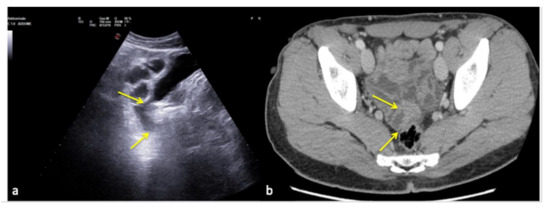

Figure 26. Coronal US scan of the left hypochondrium (a) shows partial exploration of the spleen with unrecognized traumatic injury (arrow) in a 22-year-old man investigated for trauma. On CT scan (b) it appears to be more evident (arrow).

Figure 27. Coronal US scan of the left hypochondrium (a) is strongly influenced by the breakage of the probe crystals (arrows) and does not clearly show the large splenic hematoma. On CT scan (b) the splenic hematoma appears to be more evident (arrows).